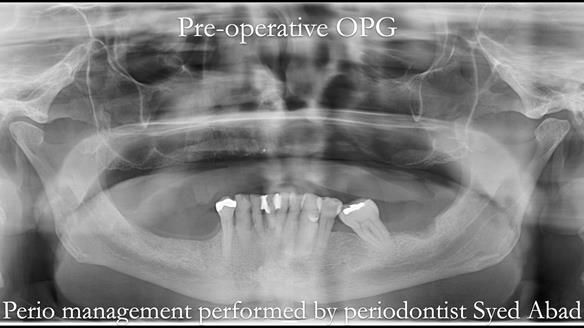

- The remaining lower 9 teeth had periodontal disease. Syed Abad, Specialist in Periodontics at the practice managed it.